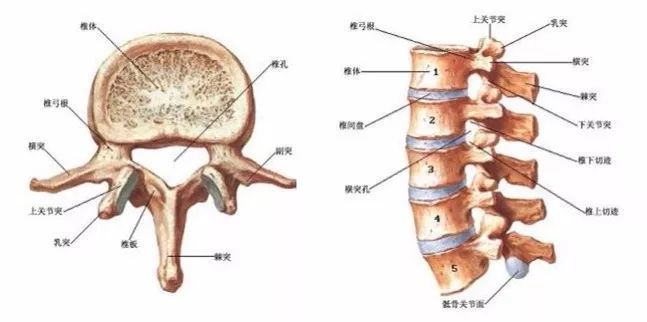

T3椎体图片

二胸椎(t2)上臂后侧痛,气喘,咳嗽,左上胸痛,心慌,心悸 第三胸椎(t3)上

凸起 c2椎棘突 c7最高 与肩胛冈内缘平行 肩胛下角水平 隆椎 t3棘突 t

即二肩胛骨内侧连线之间的椎体便是t4t3:第三胸椎的触诊需要先定位出

影像学基础详细的腰椎x线解剖及解读

在临床触摸检查时,多以c2,c7,t3,t7,t11,l4的棘突来定位,再依此推算

矢状面角度:t1:25度;t2:20度;t3:15度;t4-9:10度;t10:5度;t11-12:0度

横突|棘突|椎体|肩胛|肋骨|骶椎_网易订阅